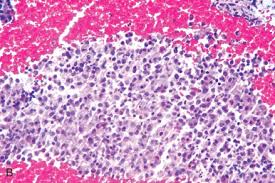

Primary peritoneal adenocarcinoma metastatic to the brain. Histopathological diagnosis was well differentiation adenocarcinoma. A type 1 excludes note indicates that the code excluded should never be used at the same time as c79.9.a type 1 excludes note is for used for when two conditions cannot occur together, such as a congenital form versus an acquired form of the same condition. adenocarcinoma is a type of malignant tumours arising from glandular tissue organs, i.e. Exposure to ultraviolet (uv) rays, like the ones from the sun or a tanning bed, affects the cells in the middle and outer layers of your skin and can cause them to. Selain itu, kanker payudara (carcinoma mammae) didefinisikan sebagai suatu penyakit neoplasma There are several different types of tumours, depending on their degree of differentiation (similarity to the original normal tissue). The kidneys are located on either side of the spine towards the lower back. Choriocarcinoma starts as a gestational trophoblastic disease and progresses to a malignancy. Tumor thickness or depth of invasion is the only size criterion predictor of nodal metastasis in carcinoma of tongue, the critical cut off values Clear cell renal cell carcinoma, or ccrcc, is a type of kidney cancer. 60 metastasis squamous cell carcinoma pada kgb. Peran usg lain adalah untuk evaluasi metastasis ke organ viseral.